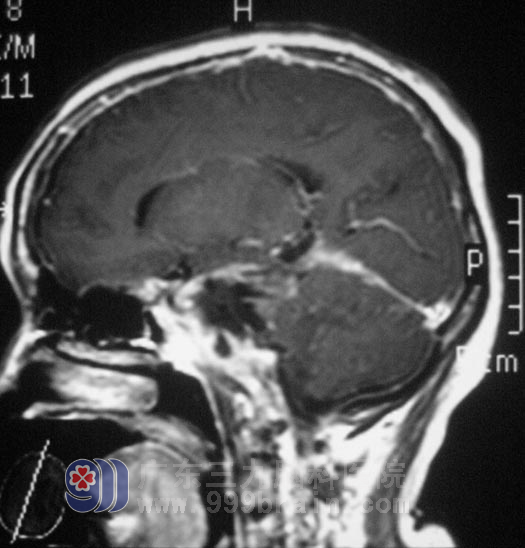

60岁的刘女士,六年前无明显诱因出现右侧肢体乏力,以上肢为甚,进行性加重,以为是风湿、疲劳引起,也就没有去医院进行治疗。一年多前开始出现吞咽困难,并且症状逐渐加重,同时伴有视物模糊,服用多种药物治疗,效果欠佳。今年2月去当地医院行头部MRI检查,提示“右侧鞍旁巨大占位性病变,大小约52.5mm×8mm×64.1mm”,原来这就是折腾了刘女士6年的病根:

入住广东三九脑科医院时,刘女士精神差,睁眼乏力,言语表达不清,嘴角稍向右偏,鼓气动作乏力。发音嘶哑、饮水呛咳、吞咽困难,悬雍垂右偏,咽反射迟钝,右侧肢体肌力III级,综合神经外科 鲁明主任详细了解病史后,结合影像资料初步考虑为脑膜瘤。7月13日,由鲁明主任主刀,在全麻下行经颞部颞下入路行鞍旁占位性病变切除术,术中见肿瘤位于右侧前中后颅窝,侵犯硬脑膜并破坏颅底骨质,范围广,内侧至海绵窦、鞍区、脑干,后至小脑幕,下至前中后颅窝底,用超声刀及双极电凝逐步切除肿瘤,海绵窦区及脑干区小部分肿瘤粘连较紧。手术后,刘女士顺利渡过水肿期、感染期,下一步就是进行康复治疗。术后经病理证实为:(右侧鞍旁)脑膜瘤,WHO I级。